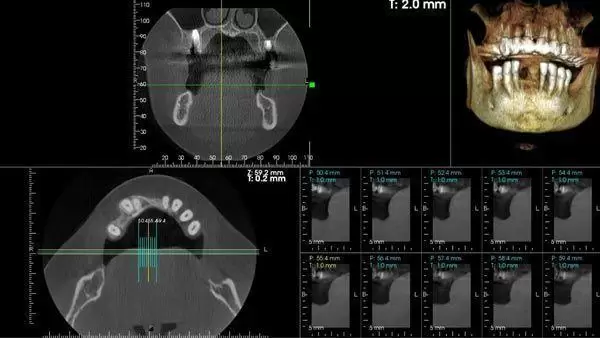

Cirugía guiada 3D para implantes dentales Barcelona

La cirugía guiada 3D permite planificar de forma digital la colocación de los implantes antes de la intervención. Gracias a esta técnica, podemos estudiar con precisión la anatomía del paciente, elegir mejor la posición de cada implante y mejorar la previsibilidad del tratamiento.

En Clínica Dental Edo, esta planificación avanzada forma parte de nuestro enfoque en implantología inteligente, orientado a combinar seguridad, precisión y personalización en cada caso. Según el briefing estratégico, la clínica trabaja con diagnóstico 3D y tecnología avanzada en implantología.

- Planificación digital del caso

- Mayor precisión quirúrgica